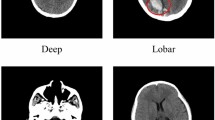

Private Dataset. The first dataset is a private dataset from a partnering hospital comprising 286 cases. Each case includes an original volumetric CT image along with corresponding masks of ICH regions. After window thresholding and normalization, we put these volume data into use. While the number of slices varies across cases, all slices maintain a consistent resolution of 512\(\times\)512 pixels, ensuring uniformity in processing and analysis.

Physionet Dataset23. The second dataset is a public dataset with 75 cases. To ensure a meaningful analysis, only cases with three or more slices containing hemorrhage regions are selected. We utilize the provided preprocessing method to standardize the data. For the segmentation task, the dataset includes original CT images along with corresponding segmentation masks. Additionally, each slice of the volumetric data has a uniform resolution of 512\(\times\)512 pixels.